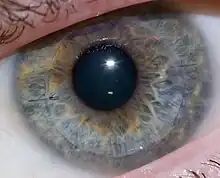

Cornea transplant approximately one week after surgery. Multiple light reflections indicate folds in the cornea, which were later resolved. | |